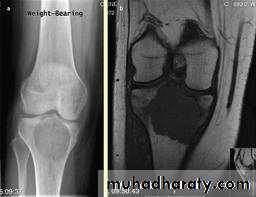

show a radiolucent area situated eccentrically at the end of a long bone and bounded by the sub- chondral bone plate.

The endosteal margin may be quite obvious, but in aggressive lesions it is ill-defined.

X-rays42

The Centre sometimes has a soap-bubble appearance.

The cortex is thin and sometimes ballooned. aggressive lesions extend into the soft tissue.43

The appearance of a ‘cystic’ lesion in mature bone, extending right up to the subchondral plate, is so characteristic

CT scans and MRI will reveal the extent of the tumour, both within the bone and beyond.